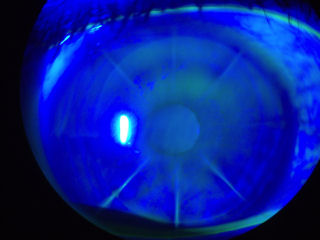

На фотографии ниже представлен глаз пациента, перенесшего операцию LASIK в 2003 году. Край лоскута LASIK все еще виден на этой фотографии 2012 года, демонстрирующей неспособность лоскута к заживлению У пациента есть болезнь сухого глаза , которые проявляются в виде сухих пятен на роговице. (Для освещения поврежденных тканей после закапывания зеленого красителя в глаз используется специальный свет). Небольшие, плохо очерченные овальные или круглые участки чуть ниже лоскута LASIK между 11:00 и 1:00 - это врастание эпителия У пациента также есть эктазия после операции LASIK Нажмите на фотографию, чтобы увеличить ее.